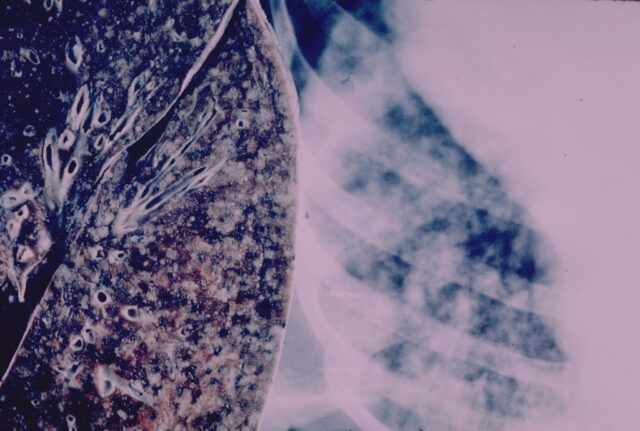

A lung with miliary tuberculosis. (Photo credit: Yale Rosen/Flickr)

International data suggests that tuberculosis cases are up to 100 times higher in prisons than in the general population due to overcrowding, promiscuity, late diagnosis, and poor ventilation. There is a significant need for tuberculosis testing and treatment in these facilities.